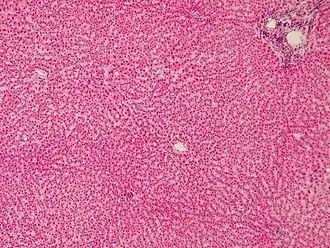

Human liver stained with hematoxylin and eosin showing hepatocytes organized into plates and lobules | |

Hepatocytes display an eosinophilic cytoplasm, reflecting numerous mitochondria, and basophilic stippling due to large amounts of rough endoplasmic reticulum and free ribosomes. Brown lipofuscin granules are also observed (with increasing age) together with irregular unstained areas of cytoplasm; these correspond to cytoplasmic glycogen and lipid stores removed during histological preparation. The average life span of the hepatocyte is 5 months; they are able to regenerate.

Hepatocyte nuclei are round with dispersed chromatin and prominent nucleoli. Anisokaryosis (or variation in the size of the nuclei) is common and often reflects tetraploidy and other degrees of polyploidy, a normal feature of 30–40% of hepatocytes in the adult human liver.[4] Binucleate cells are also common.